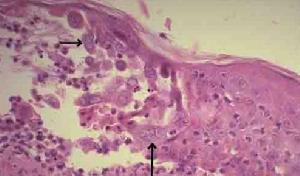

脫落細胞或皰疹基底刮片細胞學檢查,病變細胞增大有核內包涵體或呈多核巨細胞改變,雖陽性率可達60%~70%,但陽性改變非單純皰疹病變所特有。近年採用單克隆或多克隆抗體染色,特異性及敏感性均較高。

對新生兒單純皰疹病毒感染作出快速和特異性的診斷是基礎。感染可以通過人不同系列和非人類來源細胞的組織培養中分離到病毒而證實,病毒標本通常從皮膚水泡取得,口腔,眼睛和腦脊液也是產病毒的部位。在一些表現為腦病的新生兒,病毒僅能從大腦中發現。但是精確的測試(如單純皰疹病毒PCR檢測)只能在一些研究單位和特殊實驗室中進行,一般在24~48小時內可在組織培養中見到細胞病理反應,確診也可通過合適的高滴度抗血清作中和反應;用病損皮膚塗片作免疫螢光檢查,特別是使用單克隆抗體和電鏡檢查。如果無病毒學診斷設備,用病損基底部細胞,作帕氏塗片可顯示特徵性組織病理學依據(多核巨細胞和核內包涵體),但這一檢查的敏感性比培養差,並有假陽性出現。